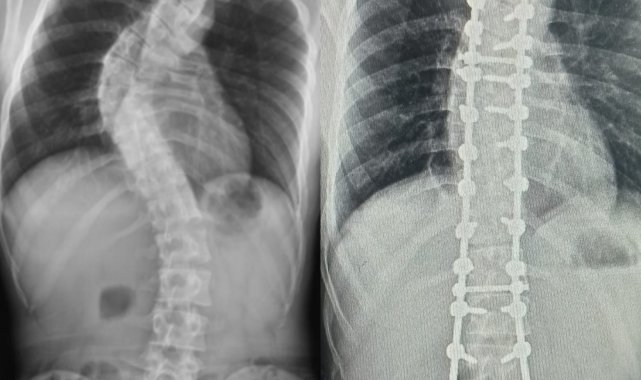

Yapılan muayene ve incelemeler sonucu hastada 73 derece skolyoz (omurga eğriliği) ve kifoz (kamburluk) tespit edilerek Ahmet Akan'a ameliyat önerildi. Samsun Üniversitesi Tıp Fakültesi Ortopedi ve Travmatoloji Anabilim Dalı Öğretim Üyelerinden Dr. Öğr. Üyesi Ömer Bozduman, deneyimli ameliyat ve anestezi ekibi eşliğinde görev yaptığı Samsun Eğitim ve Araştırma Hastanesi'nde 7 saat süren başarılı bir skolyoz ameliyatı gerçekleştirdi.

Hasta ile ilgili bilgi veren Dr. Öğretim Üyesi Ömer Bozduman, "Hastamız artan sırt ağrıları ve omurga eğriliğinin ilerlemesi şikâyetiyle kliniğimize başvurdu. İnceleme ve değerlendirmelerimiz sonucu ameliyat kararı verdik. 7 saat süren skolyoz ameliyatını takiben 12 saat sonra hastamız kaldırılıp yürütüldü. Ameliyat sonrası nörolojik olarak hiçbir sorunu yok. Eğriliği tamamen düzeldi, boyu uzadı. Şu an kendisi yürüyüp gezebiliyor. Hastayı 5 gün sonra taburcu edip evine gönderiyoruz. Her ameliyatta olduğu gibi skolyoz ameliyatlarında da ekip çalışması çok önemlidir. Uzun süren bu ameliyatı, hastanemizin özverili ameliyat ve servis hemşireleri ve deneyimli anestezi ekibi ile gerçekleştirdik" dedi.